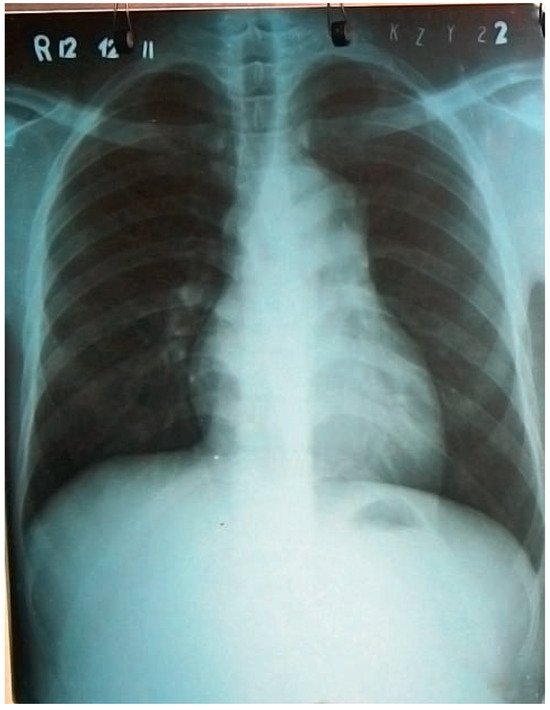

Surviving Acute Traumatic Transection of the Ascending Aorta and Proximal Aortic Arch

We report a 22-year-old male patient who survived clinically unapparent acute traumatic transection of the distal ascending aorta and the proximal aortic arch. Two months after the incident, the patient presented with hoarseness, respiratory distress and severe venous congestion of the upper part [...] Read more.

We report a 22-year-old male patient who survived clinically unapparent acute traumatic transection of the distal ascending aorta and the proximal aortic arch. Two months after the incident, the patient presented with hoarseness, respiratory distress and severe venous congestion of the upper part of the body. Echocardiography demonstrated a huge mediastinal tumour, dilated right heart chambers as well as pericardial tamponade. In the computed tomography (CT), scan rupture of the distal ascending aorta and the proximal aortic arch was found. The preserved adventitial layer, preventing immediate death from exsanguination or pericardial tamponade, distended over time forming a false aneurysm with a diameter of 9 cm, with its main part being located to the left of the trachea. Systolo-diastolic motion of the thin-walled false aneurysm led to the typical pulse-synchronous horizontal motion of the thyroid cartilage and the trachea, described as the Cardarelli sign. As a result of systolic expansion and diastolic shrinking of this huge false aneurysm, the arterial blood pressure curve of the patient perfectly imitated the blood pressure curve seen only with a properly timed intra-aortic balloon pump. In addition, the systolic blood pressure repeatedly compressed the main pulmonary trunk, which crossed the bottom of the false aneurysm, consecutively leading to clinically apparent right heart failure, serous pericardial effusion and pericardial tamponade. The patient successfully underwent ascending aortic and proximal aortic arch replacement using deep hypothermia, circulatory arrest and selective antegrade cerebral perfusion. Full article